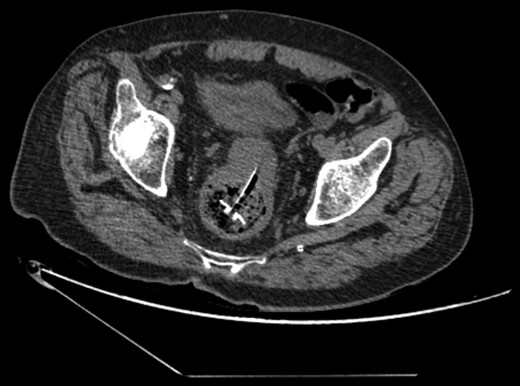

A 68-year-old male nursing home resident presented following dislodgement of a percutaneous endoscopic colostomy (PEC) tube originally sited to prevent recurrent sigmoid volvulus. Computed tomography demonstrated tube migration into the lumen of the recto-sigmoid junction, where it remained for 12 days before passing spontaneously. During this period, the patient remained asymptomatic; the residual colocutaneous fistula functioned as a decompressive valve. Originally, the patient was due to be discharged with early flexible sigmoidoscopy follow-up. However, complex social issues delayed discharge. During his admission, a second PEC tube was successfully inserted next to the previous colostomy site without complication. This is an unusual case and no similar episodes of asymptomatic PEC migration have been reported. We demonstrate that such cases may be offered an appropriate trial of conservative management. Here, we describe our experience and critically appraise the literature.

The patient remained asymptomatic with a soft, non-tender abdomen. The only abnormal clinical finding was the absence of a PEC tube from a patent periumbilical colostomy site.

The patient remained well and the PEC tube passed spontaneously on Day 12, during a bowel motion.

Tube migration leading to perforation and frank peritonitis has been described elsewhere [10]. However, there are no cases of asymptomatic dislodged PEC tubes. Following discussion with gastroenterology and colorectal surgery, the decision was made to let the PEC pass spontaneously or remove it during early follow-up flexible sigmoidoscopy. The PEC tube was naturally expelled on Day 12 without complication.